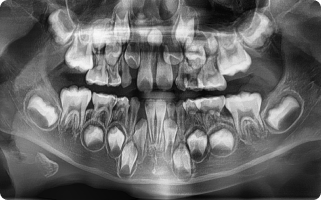

구강 검진, 촉진, 교합 검사 또는 파노라마, CBCT, MRI 촬영을 통해

눈에 보이지 않는 부위까지 선명하게 관절 및 디스크 상태를 확인합니다.

정밀 진단

- 구강 검진, 촉진, 교합 검사

- 필요 시 파노라마, CBCT, MRI 촬영을 통해 관절 및 디스크 상태 확인